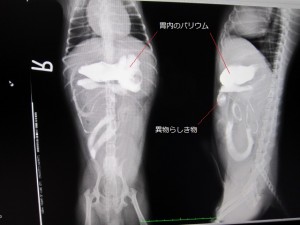

術前

術前のレントゲンです。

バリウム投与24時間後も結腸までバリウムが流れませんでした。